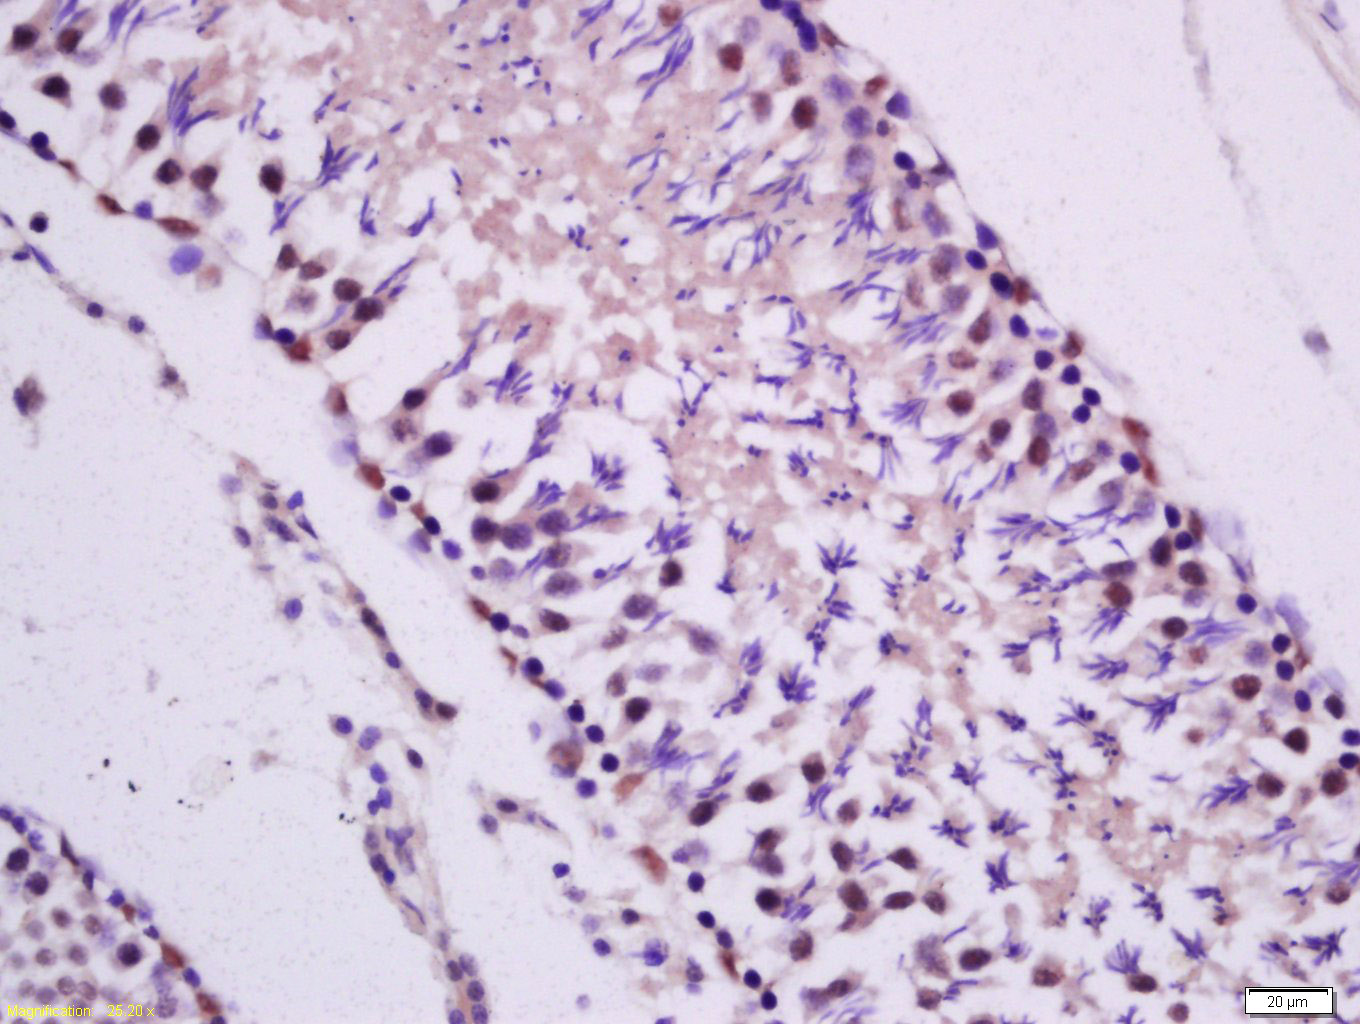

Tissue/cell: rat testis tissue; 4% Paraformaldehyde-fixed and paraffin-embedded; Antigen retrieval: citrate buffer ( 0.01M, pH 6.0 ), Boiling bathing for 15min; Block endogenous peroxidase by 3% Hydrogen peroxide for 30min; Blocking buffer (normal goat serum,C-0005) at 37℃ for 20 min; Incubation: Anti-PKC epsilon Polyclonal Antibody, Unconjugated(bs-2329R) 1:200, overnight at 4°C, followed by conjugation to the secondary antibody(SP-0023) and DAB(C-0010) staining